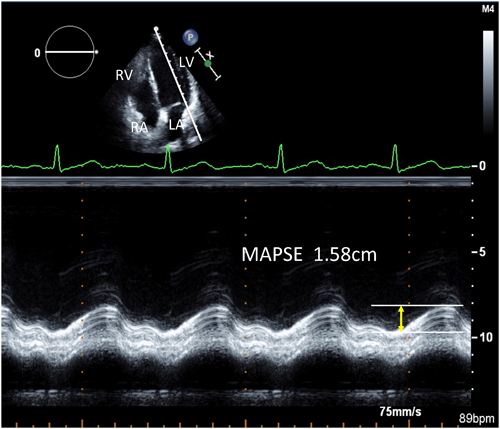

僧帽弁輪収縮期移動距離(MAPSE)

ここまでTDIを用いた長軸機能に関して概説してきたが,M-modeを用いても長軸機能の評価は可能である.すなわち,心尖部四腔断面で外側僧帽弁輪にカーソルを設定し,その移動距離を測定する(Figs. 11, 12).この指標はs′波を時間積分したことになり,最も簡単な左室長軸機能指標と言える.測定に際しては,弁輪運動方向がM-modeのビーム方向に平行となるよう工夫する.

Pediatric Cardiology and Cardiac Surgery 32(2): 70-77 (2016)

Fig. 11 Measurement of MAPSE using the M-mode echocardiography

In the apical 4-chamber view, MAPSE is measured as the longitudinal mitral annular motion from the apex using M-mode echocardiography. It is measured as the distance between the peak and the bottom of the M-mode tracing curve. LA=left atrium; LV=left ventricle; RA=right atrium; RV=right ventricle; MAPSE=mitral annular plane systolic excursion.